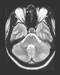

MRI of the eyeball and optic nerve CT of the eyeball and optic nerve MRI of eye muscles Review the actions of the extraocular muscles from an anterior view of the bulb.